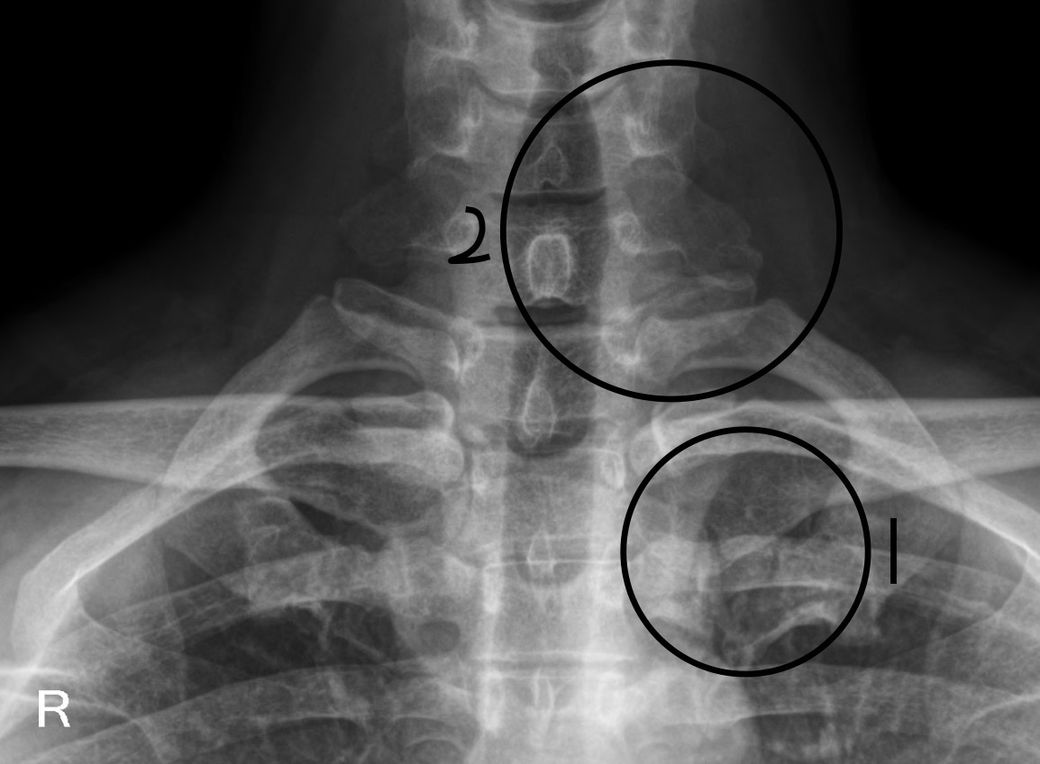

궁금해서 엑스레이 파일을 받아서 제가 직접 보니 동그라미 친 1번에 다른 골절도 보이는 것 같고 통증이 지속적으로 느껴지는 2번 파열되서 부은 부분도 더 커진 느낌입니다.

1번 부분이 사고났던 7번 횡돌기인가요? 아니면 그냥 아무것도 아닌가요? 아니면 골절인가요?

표시해주신 1번 동그라미 부분 같은 경우 7번째 목뼈의 횡돌기일 가능성이 높으며 엑스레이상 골절의 흔전은 정확히 확인하기 어려울 것으로 생각되며 6개월 째 통증이 지속되고 있고 부종이 이 있다면 기타 연부조직의 손상 또는 신경 자극의 가능성도 존재하기 때문에 가까운 병원에 방문하시어 추가적인 검사를 통해 정확한 상태 검사 받아보시고 상태에 맞는 치료 및 처치등을 받아보시는게 좋을 것으로 생각됩니다.

1번 부부닝 7번 경추 횡돌기일 가능성이 높으며 엑스레이 상 골절 흔적이나 치유 상태는 전문가가 직접 판단해야 정확합니다. 6개월째 지속되는 통증과 부종 확대는 골절 치유 지연이나 연부조직 손상, 신경 자극 가능성을 시사하니 주의가 필요합니다!

1번으로 표시된 부위는 흉추뼈로 보여지며 갈비뼈 및 다른 뼈들과 겹치는 부분이기에 골절로는 정확한 확인이 어렵습니다.

사진에서 표시해주신 1번 부위는 연부조직이 겹쳐 보이는 부분이나 과거의 외상을 당했던 부위로 의심해볼 수 있지만, 엑스레이만으로는 정확한 판단이 어려울 수 있습니다.